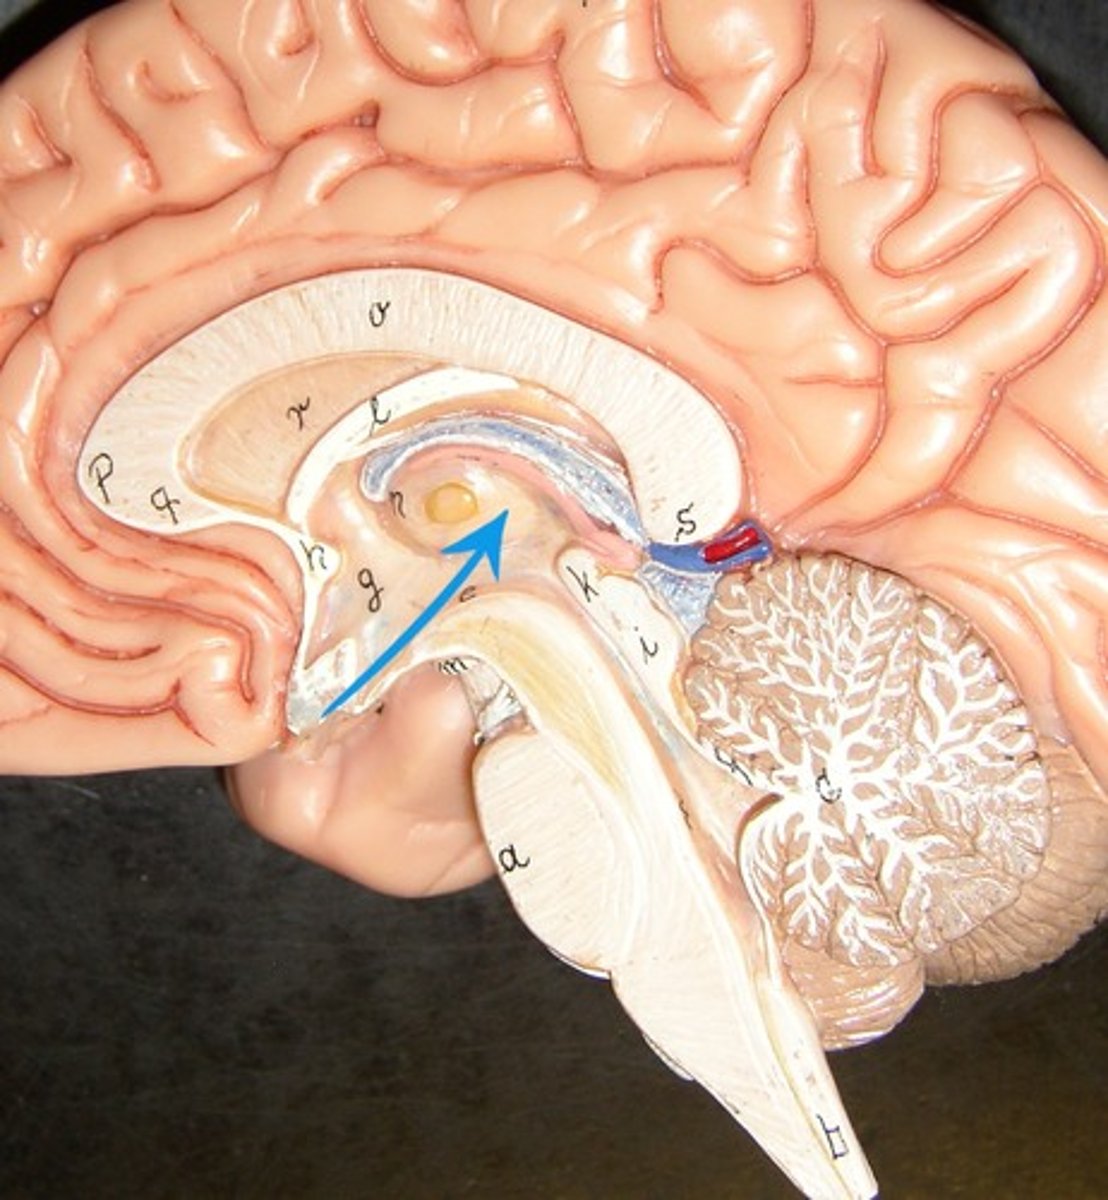

pineal body (pineal gland)

right and left lateral ventricles

third ventricle

fourth ventricle

cerebral aqueduct (mesencephalic aqueduct)

interventricular foramen

corpus callosum

septum pellucidum

fornix